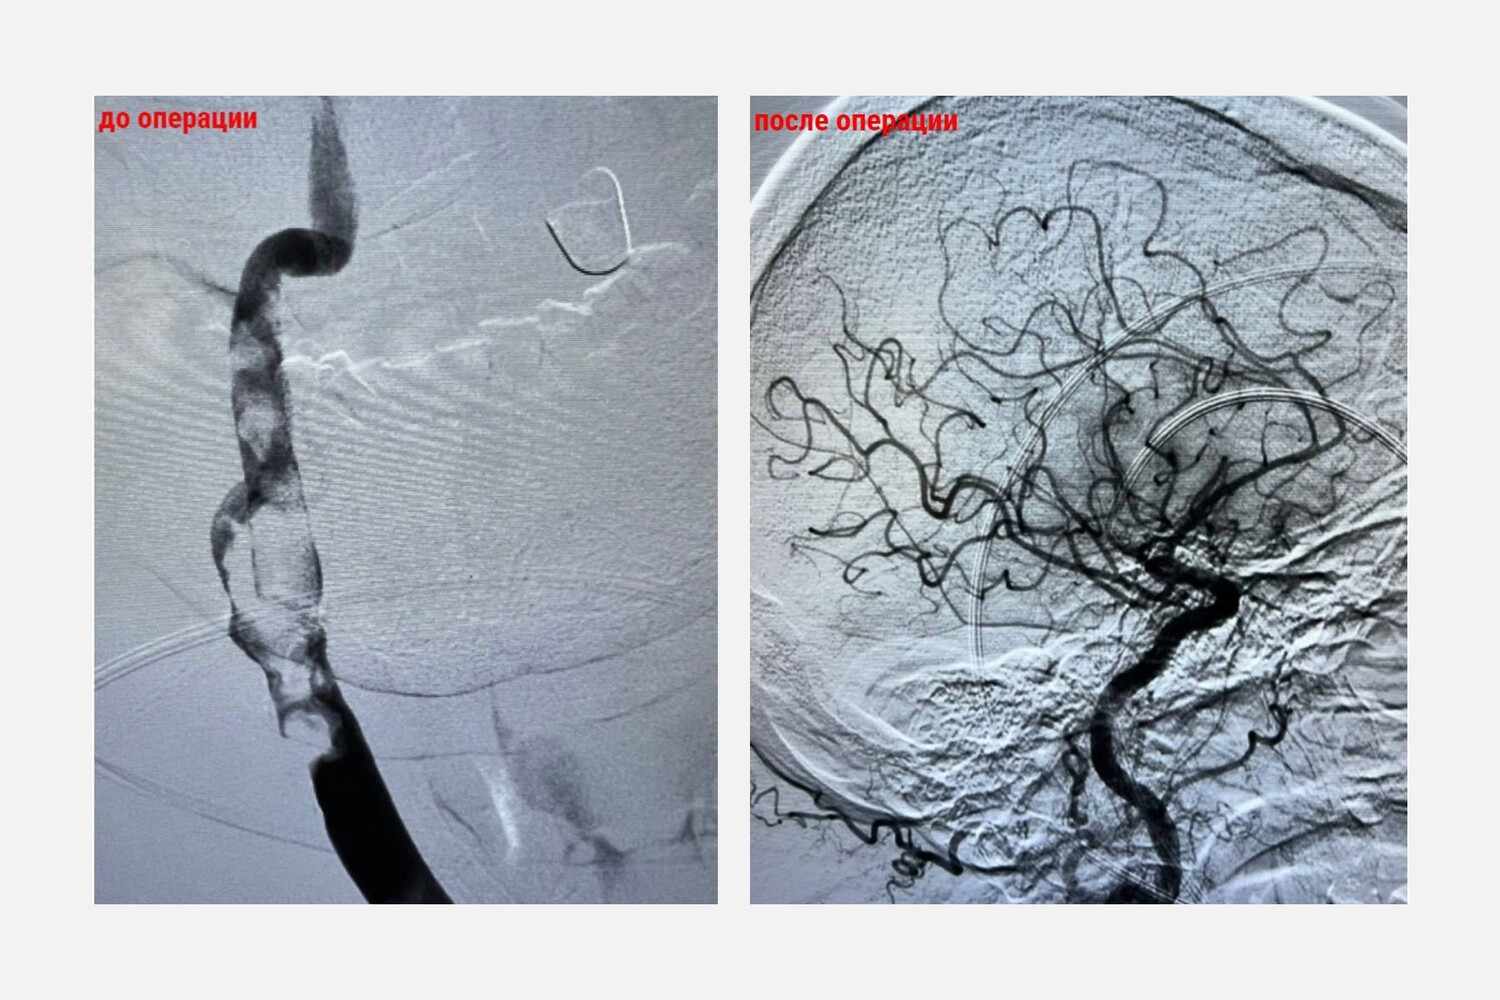

В Красногорске, Московская область, врачи удалили из мозга 65-летнего мужчины трехсантиметровый тромб, который образовался после самостоятельной отмены лекарств, сообщается в Telegram-канале Осторожно, Москва.

Врачи провели операцию, в ходе которой через небольшой прокол в бедре ввели специальный катетер к сосудам головного мозга, после чего удалили трехсантиметровый тромб. Тромбэкстракция заняла около 45 минут.